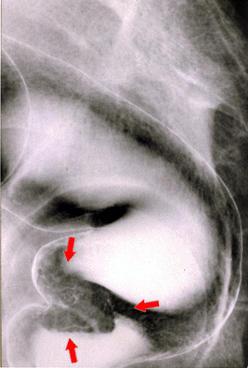

고유근층에 침윤하고、간전이를 동반한 2.5cm 크기의 직장 카시노이드 (63세、남)

[Image-ID:1315]

카시노이드종양/

대장/직장

X-P

25~29

종양의 심달도

mp